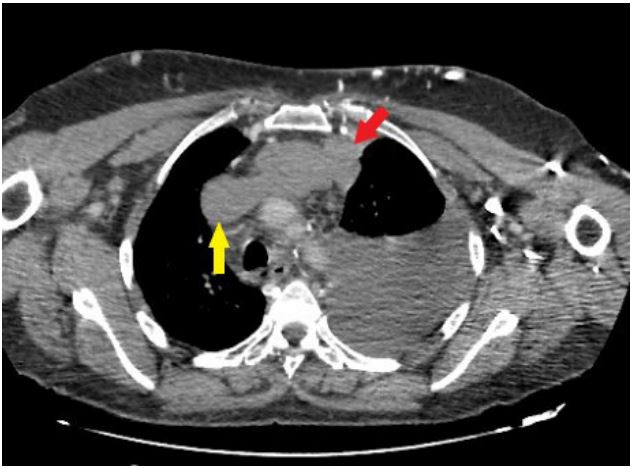

A 51‐year‐old women was hospitalized to start chemotherapy for small cell lung cancer diagnosed one months earlier. She underwent Computed Tomography (CT) of the chest and abdomen to re‐evaluate the progression of the lung tumour. Contrast-enhanced CT of the chest indicated an invasive anterior left lung tumour that caused an obstruction of the Superior Vena Cava (SVC) (Figure 1). Contrast-enhanced CT of the abdomen revealed an intense focal wedge-shaped homogeneous enhancement area in the quadrate lobe of the liver, which is known as the hot spot sign (Figure 2). Focal hepatic hot spot sign was first described by Ishikawa in 1983. The sign can be observed on technetium 99m (99mTc) Sulphur colloid scans or on contrast, material enhanced CT scans [1]. Hot spot sign is caused by portosystemic venous shunting between the superior vena cava and the left portal vein via the internal mammary and paraumbilical veins along the ligamentum teres, secondary to superior vena cava obstruction. The hot spot is created by areas of focally increased blood flow that result from this shunting [2]. Stanford and colleagues classified SVC syndrome into four types - type I and type II referred as supra-azygous partial and near complete obstruction of SVC with antegrade flow in azygous vein. Type III is defined as complete obstruction of SVC with reversal of azygous blood flow and type IV as complete obstruction of SVC and azygous system with development of chest wall collaterals [3]. This sign has been reported in Budd-Chiari syndrome, the causes of SVC syndrome (neoplasms of the thorax as lung carcinoma and lymphoma, Vasculo‐Behcet’s disease, fibrosing mediastinitis, and luetic aneurysm), and masses of the liver (abscess, haemangioma, focal nodular hyperplasia, and hepatocellular carcinoma) [4].

Figure 1: